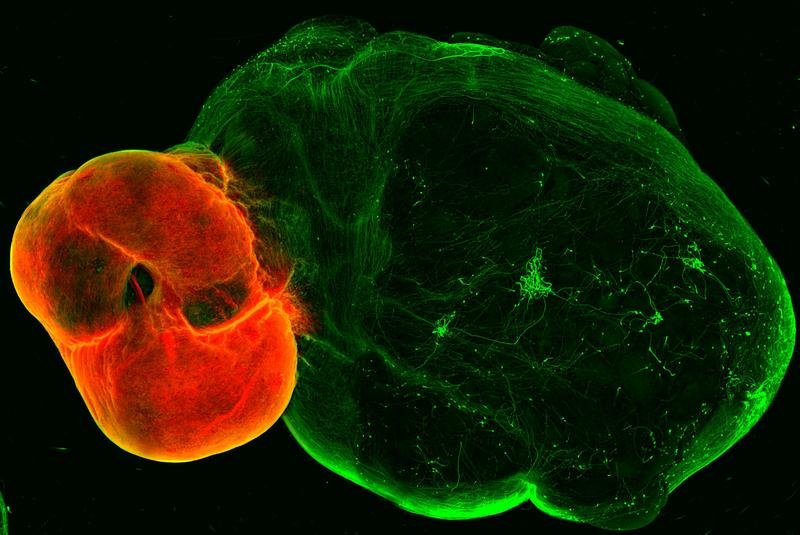

Dopaminerge Neuronen in einem Gehirnorganoid.

Dopaminerge Neuronen in einem Gehirnorganoid. Daniel Reumann/IMBA

Ein neues Organoidmodell des Belohnungszentrums in unserem Gehirn gibt Aufschluss über dessen komplizierte Funktionsweise und seinen möglichen Einfluss auf Parkinson-Erkrankungen. Das Modell, das von der Gruppe von Jürgen Knoblich am Institut für Molekulare Biotechnologie (IMBA) der Österreichischen Akademie der Wissenschaften entwickelt wurde, bildet die Struktur, Konnektivität und Funktionalität des dopaminergen Systems nach. Die Studie enthüllt auch die anhaltenden Auswirkungen von chronischem Kokainkonsum auf das dopaminerge System.

Das Team entwickelte zunächst Organoidmodelle des so genannten ventralen Mittelhirns, des Striatums und des Kortex - der Regionen, die durch Neuronen im dopaminergen System verbunden sind - und entwickelte dann eine Methode, um diese Organoide zu fusionieren. Wie im menschlichen Gehirn senden die dopaminergen Neuronen des Mittelhirn-Organoids Projektionen ins Striatum und Kortex-Gewebe aus. „Etwas überraschend beobachteten wir ein hohes Maß an dopaminerger Innervation sowie die Bildung von Synapsen zwischen dopaminergen Neuronen und Neuronen in Striatum und Kortex“, berichtet Reumann.